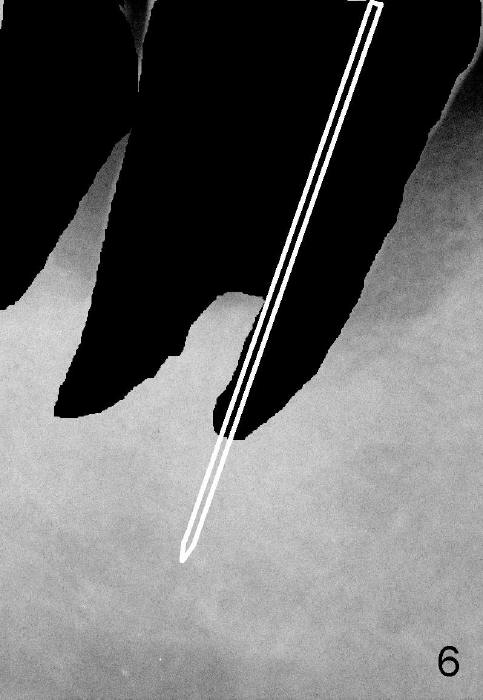

In brief, a large implant is to be placed in the mesial socket of #31.  In order to increase primary stability and save autogenous bone (septal bone (Fig.5 S, drawing from Fig.4 after extraction), a pilot drill is used to start osteotomy in the mesial socket (Fig.6 white lines), followed by insertion of osteotomes (Fig.7 white lines, combined with drills).  The latter are mainly used to push the septum distally (red arrow).  By the time a large implant is placed (Fig.8 green lines), the septum is further pushed distally (red arrow).  The remaining distal socket is then filled with bone graft (red circles).  How does the surgery end up with?